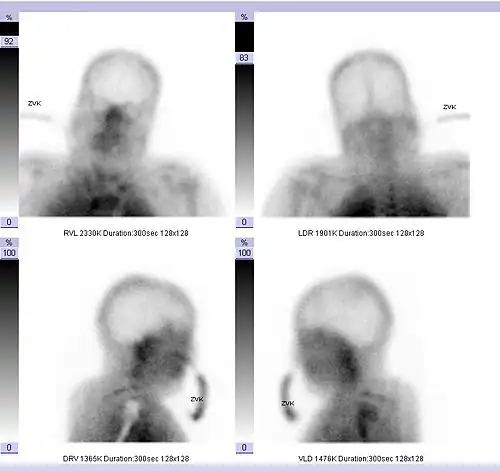

- Ein mittels zerebraler Hirnperfusionsszintigraphie oder Doppler-Sonographie festgestellter Durchblutungsstopp in allen hirnversorgenden Gefäßen. Bei der Perfusionsszintigraphie wird eine schwach radioaktiv markierte Substanz injiziert und ihre Verteilung im Gehirn verfolgt. Bei intakter Hirndurchblutung lässt sich die Markierungssubstanz über Stunden in den durchbluteten Hirnregionen nachweisen. Bei einem Hirntoten hingegen stellt sich die Schädelhöhle infolge eines Abbruchs der gesamten Hirndurchblutung „leer“ dar. Bei der Dopplersonographie werden die Hirnbasisarterien beschallt. Anhand der Reflexion des Schallsignals wird die Blutflussgeschwindigkeit in den Hirngefäßen gemessen. Die Dopplersonographie darf nur von einem hierin erfahrenen Untersucher vorgenommen werden und muss mindestens zweimal im Abstand von wenigstens 30 Minuten erfolgen.